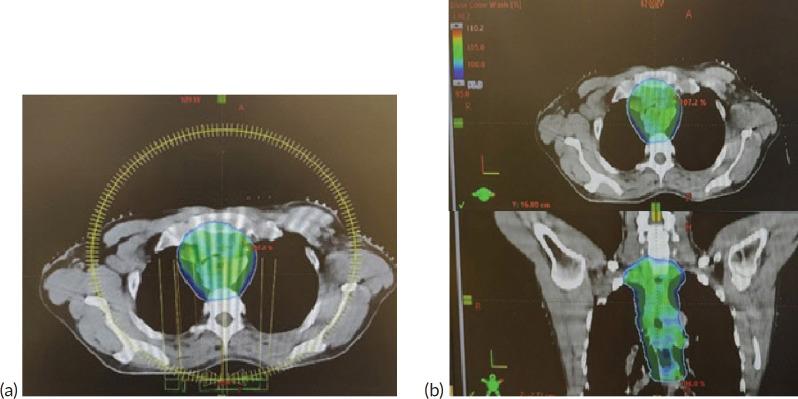

一名晚期食管癌致恶性中央气道梗阻的插管患者在呼吸机支持下接受放射治疗:病例报告

与气道直接或间接相关的恶性肿瘤可导致一种致命状况,称为恶性中央气道阻塞(MCAO)。传统上,腔内和腔外MCAO均采用支气管镜介导的疗法进行治疗,但对于不适合支气管镜干预的患者,选择非常有限,尤其是当患者因阻塞需要呼吸机支持时。很少有需要呼吸机支持的肺癌合并MCAO患者接受放射治疗(RT)并取得了显著效果。尽管将此类患者转出重症监护病房存在多种风险,但当RT被认为是唯一可能的解决方案时,仍必须采取这些措施。在这例罕见的需要呼吸机支持并接受RT治疗的食管癌合并MCAO患者中,我们展示了RT如何用于增加患者拔管的可能性。因此,在该病例中,通过RT旨在并实现了呼吸缓解和拔管。